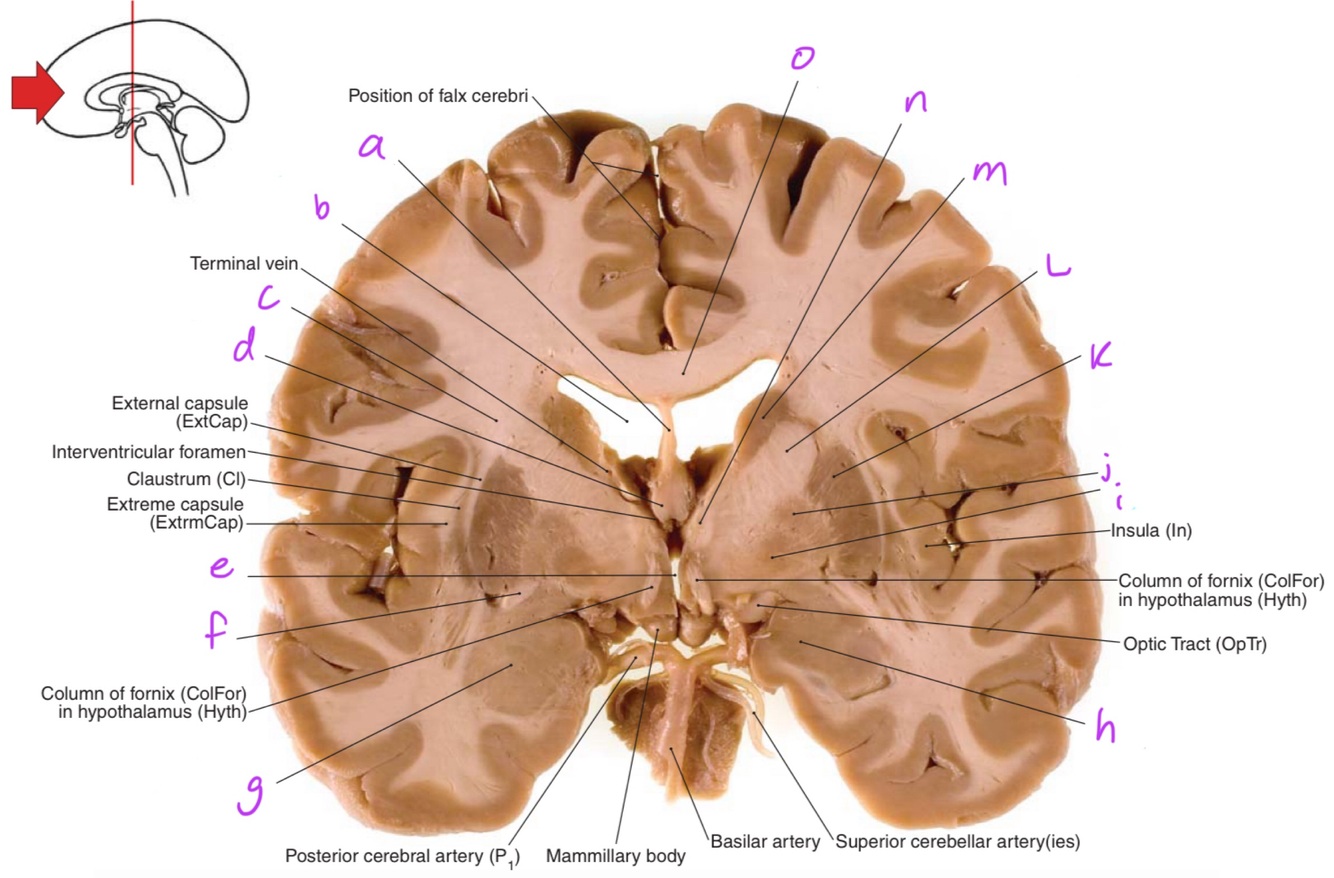

25

c

Corona radiata

26

d

Column of fornix

27

e

Third ventricle

28

f

Anterior commissure

29

g & h

amygdala (nuclear complex)

30

i

globus pallidus internus

31

j

globus pallidus externus

32

k

Putamen

33

L

Internal capsule genu

34

m

head of caudate nucleus

35

n

Anterior tubercle of thalamus

36

o

Body of corpus callosum